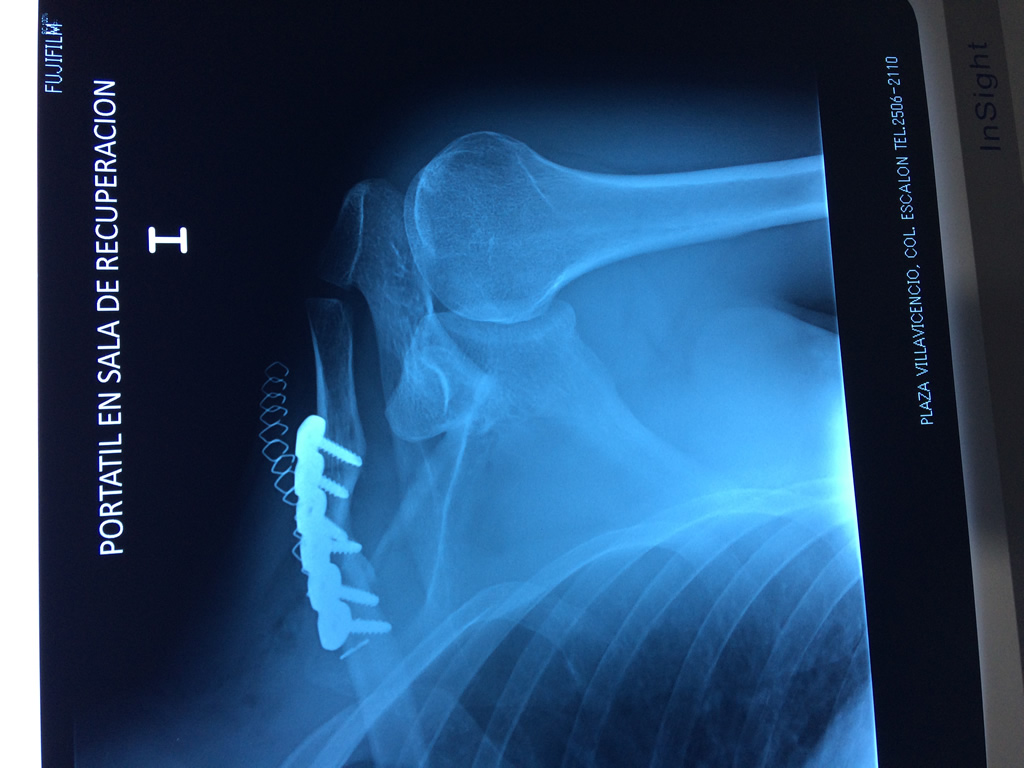

Cirugias en El Salvador - Clavícula